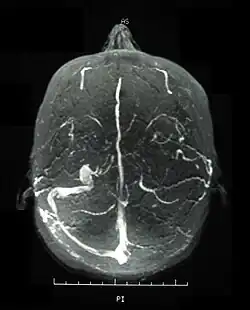

Brain

Central nervous system (CNS) involvement most often occurs as a chronic meningoencephalitis. Lesions tend to occur in the brainstem, the basal ganglia and deep hemispheric white matter and may resemble those of multiple sclerosis (MS). Brainstem atrophy is seen in chronic cases.

Neurological involvements range from aseptic meningitis to vascular thrombosis such as dural sinus thrombosis and organic brain syndrome manifesting with confusion, seizures, and memory loss. Sudden hearing loss (sensorineural) is often associated with it.[4] They often appear late in the progression of the disease but are associated with a poor prognosis.

Visual acuity, or color vision loss with concurrent mucocutaneous lesions or systemic Behçet's disease symptoms should raise suspicion of optic nerve involvement in Behçet's disease and prompt a work-up for Behçet's disease if not previously diagnosed in addition to an ocular work-up. Diagnosis of Behçet's disease is based on clinical findings including oral and genital ulcers, skin lesions such as erythema nodosum, acne, or folliculitis, ocular inflammatory findings and a pathergy reaction. Inflammatory markers such ESR, and CRP may be elevated. A complete ophthalmic examination may include a slit lamp examination, optical coherence tomography to detect nerve loss, visual field examinations, fundoscopic examination to assess optic disc atrophy and retinal disease, fundoscopic angiography, and visual evoked potentials, which may demonstrate increased latency. Optic nerve enhancement may be identified on Magnetic Resonance Imaging (MRI) in some patients with acute optic neuropathy. However, a normal study does not rule out optic neuropathy. Cerebrospinal fluid (CSF) analysis may demonstrate elevated protein level with or without pleocytosis. Imaging including angiography may be indicated to identify dural venous sinus thrombosis as a cause of intracranial hypertension and optic atrophy.